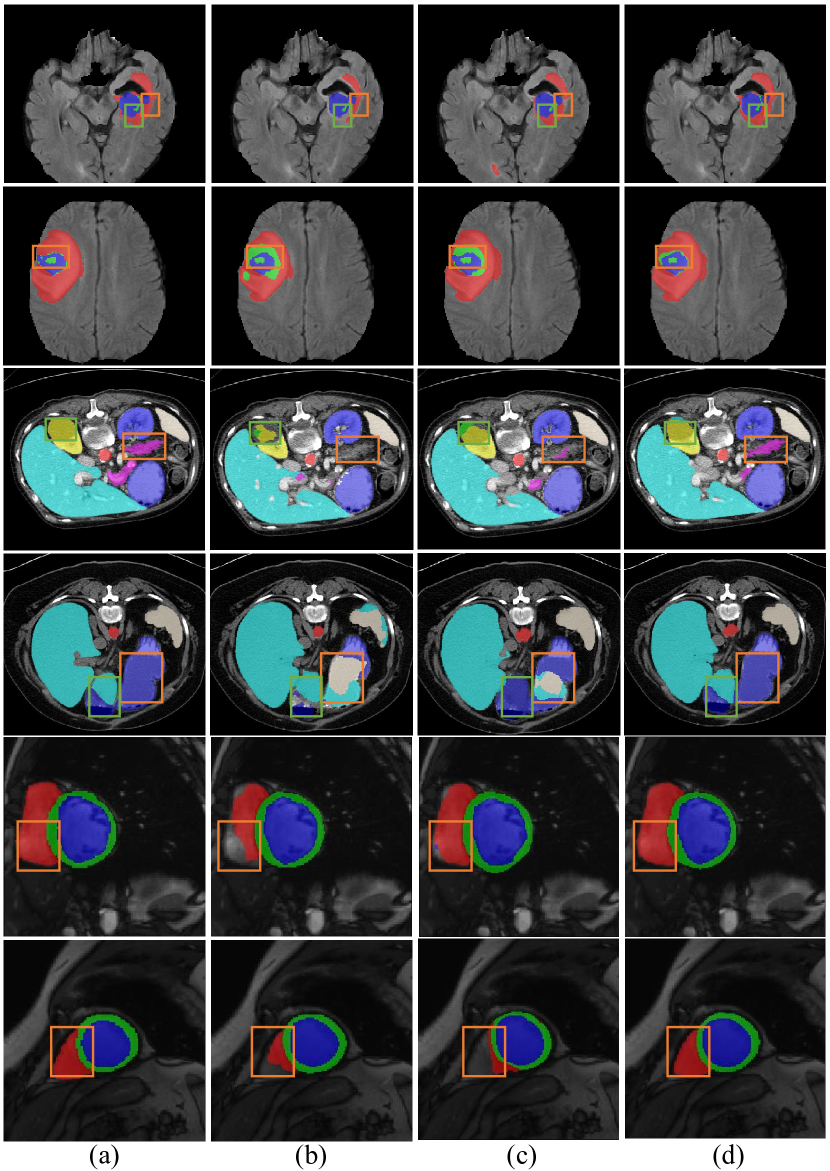

Refer to caption

Figure 7: Qualitative results from the MSD Brain, Synapse and ACDC datasets. We compare (a) Ground Truth with the outputs of (b) ResUNet, (c) TransUNet and (d) Ours.

Results of our model and other state-of-the-art methods are shown in Table I 111Results of UNet, VNet, AHNet, Att-UNet, SegResNet and UNETR are from [14], results of two nnUNet models are from [23], results of DiNTS are from [17].. On the MSD BrainTumour Dataset, our model achieves the best performance of 74.75% Dice similarity coefficient (DSC) with 80.73%, 63.23%, and 80.29% on edema, non-enhancing tumor, and enhancing tumor respectively. When comparing with our baseline model ResUNet, we achieve a significant increase of 2.83%. Compared with nnUNet [23] 2D version, which also builds upon the U-Net architecture, our method obtains an improvement of 3.19%. Moreover, when compared with ensemble 3D nnUNet, we also outperform by 0.86%. We also make a comparison between state-of-art Transformer-based models including recent 3D network UNETR [14] and 2D network SwinUNet [4] which we outperform by a margin of 2.94% and 1.55% on average DSC respectively. To provide a demonstration of results on MSD Brain dataset, the first two rows of Figure 7 offer a sample of (a) gt label, (b) ResUNet, (c) TransUNet, and (d) Ours. Our baseline ResUNet model shows to be under-segmented prone, i.e. the first row of (b) shows an incomplete segmentation region while transformer-based models, i.e. TransUNet and Ours, can produce more complete and accurate results via the establishment of long-range dependencies. We can also see that both ResUNet and TransUNet face the problem of providing false positive predictions, i.e. the second row (b) and (c) show a false positive prediction of ET instead of NET (gt). Compared with TransUnet, our model shows great performance in local and marginal regions. This could be attributed to pixel-level correlation in the local window that could better model the local features.

Experiment on Synapse dataset (Table II) demonstrates the effectiveness and generalization ability to multi-organ tasks of our upsample method. We make comparison with baseline model ResUNet, recent work TransUNet [5] and SwinUNet[4] where our method outperforms ResUNet by 5.41%, TransUNet by 2.92% and SwinUNet by 1.27% on average DSC 222Results of V-Net, DARR, R50 U-Net, R50 Att-UNet, R50 ViT and TransUNet are from [5].. Moreover, we make a comparison on Hausdorff (HD) metrics which measures models’ sensitivity to edge segmentation. As per the table, we also achieve a state-of-the-art performance of 18.50. Specifically, We achieve the best performance on Kidney(L) with 84.47%, Kidney(R) with 81.04%, Liver with 94.40%, Pancreas with 61.01%, and Stomach with 79.35%. This experiment shows our model’s ability to generalize to multiple organs’ segmentation. To provide a demonstration of results on the Synapse dataset, the middle two rows of Figure 7 offer a sample of (a) gt label, (b) ResUNet and (c) TransUNet, and (d) Ours. From the graph presented, we can also notice the same problem mentioned in Section IV-C1, incomplete prediction compared with gt, i.e. in the orange region of the third row, (b) shows no positive prediction and (c) shows little positive predictions, and misclassification of the label, i.e. in the green and orange rectangle of forth row, both (b) and (c) make false positive predictions.

Table IV demonstrates our model’s performance on ACDC dataset comparing with state-of-the-arts 333Results of R50 U-Net, R50 Att-UNet, ViT-CUP, R50-ViT-CUP, and TransUNet are from [5], results of SwinUNet is from [4].. On ACDC, we achieve more than 2 points improvement on a benchmark dataset with an average DSC of 90%+, which we consider quite tremendous on such dataset. It’s worth mentioning that after being carefully tuned, ResUNet is capable of achieving a performance of 90.06%, even higher than other state-of-the-arts such as SwinUNet and TransUNet. However, our model can outperform it by nearly 2 points in DSC. The bottom two rows of Figure 7 offers a sample of gt label(a), ResUNet(b) and TransUNet(c) and Ours(d) from ACDC dataset. We can also observe an incomplete segmentation problem from (b) and (c) of the two rows and our more complete results. This also proves that our method can maintain and even enrich the information in feature maps during upsample process.